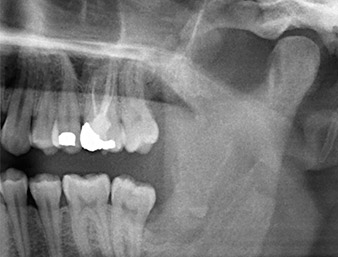

Ya en la ortopantomografía, se constató que había un resto radicular de la región 38 muy cerca del nervio alveolar inferior (figura 1). La raíz se había fracturado durante la osteotomía, pero el primer odontólogo que había tratado al paciente no había extraído esta debido a la presencia de dolor durante la operación.

Ortopantomografía

Imagen 1: Ortopantomografía 6 meses después de la osteotomía del diente 38: el resto radicular se encontraba cerca del nervio alveolar inferior.

En la imagen en 3D (tomografía volumétrica digital) se constató que el resto radicular se encontraba muy desplazado en sentido distocaudal en la transición situada entre la porción horizontal y la ascendente del maxilar inferior (figura 2).

TVD transversal

Imagen 2: Representación de una TVD transversal del resto radicular en el espacio retromolar.